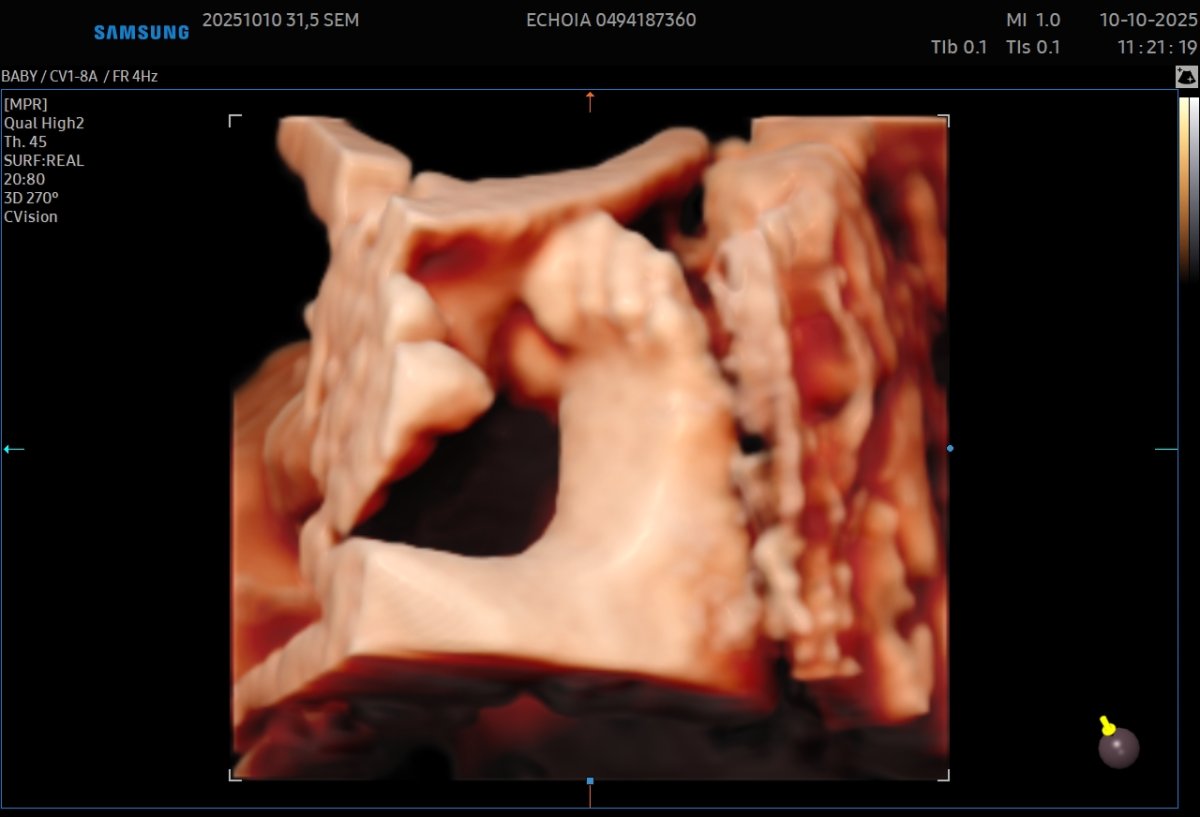

Gallerie de photos